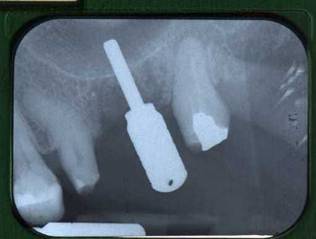

Figure 2

Rx after 26 extraction and following rehabilitation with fixed partial prosthesis.

An explorative surgery was planned in order to evaluate the presence of a possible communication.

The fixed partial prosthesis was removed and the contiguous mucosa appeared healthy.

A buccal full thickness flap was harvested and the presence of a small OAF was verified. (Fig.3).

Figure 3

Flap elevation.

After the evaluation of OAF dimensions (Fig. 4), the surgical procedure was conducted by performing an incision on the bone tissue surrounding the lesion with bone drills and by harvesting a squared wedge bone on the alveolar ridge, in order to avoid the persistence of fibrotic tissue and to permit an adequate bleeding.

Figure 4

Demonstration of OAF existence by pin.